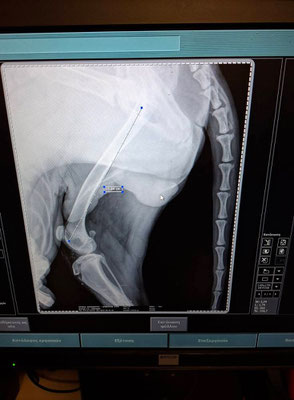

Markos (* 11/2024) hatte keinen leichten Start ins Leben. Er wurde von einem Auto erfasst und schwer verletzt. Die Fahrerin brachte ihn zwar sofort zum Tierarzt, doch danach verschwand sie spurlos – ohne sich um die Kosten zu kümmern oder zu fragen, wie es mit Markos weitergeht. Die Diagnose war erschütternd: Beide Hinterbeine waren gebrochen.

Markos musste operiert werden und verbrachte viele Tage in der Klinik. Trotz seiner schweren Verletzungen war es ein kleines Wunder, dass er nach den Operationen wieder laufen konnte. Der Tierarzt bat uns, Markos bei uns im Tierheim aufzunehmen, um ihm die Chance auf ein liebevolles und glückliches Leben zu geben – und diese Chance möchten wir ihm unbedingt ermöglichen!

Markos wurden die Metallplatten aus den Beinen entfernt. Nun befindet sich nur noch ein langer Nagel in einem der Beine, der mit dem Knochen mitgewachsen ist und dauerhaft dort bleiben wird. Ein Bein ist etwas kürzer als das andere, was zu einem leichten Hinken führt. Es besteht die Möglichkeit, dass er in der Zukunft eine weitere Operation benötigen wird. Aktuell geht es ihm jedoch gut – er läuft, rennt und spielt ganz normal. Mit seinen Artgenossen versteht er sich wunderbar.